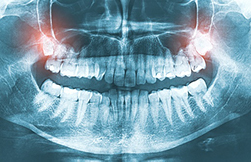

X-ray image of wisdom teeth at Surprise Oral & Implant Surgery. Wisdom teeth are the third and final set of molars that typically erupt in the late teens or early twenties. However, not everyone has wisdom teeth, and for some people, they may cause problems like crowding, impaction, or infection. In these cases, wisdom tooth extraction may be necessary.